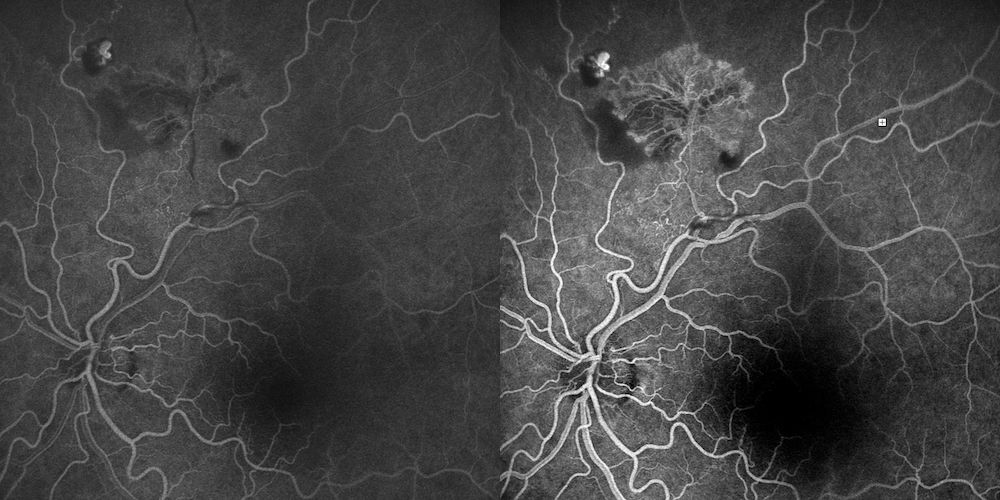

Retinografia a Colori

L’esame del fundus dell’OS ha evidenziato, in sede superotemporale, lungo l’arcata vascolare superiore, un complesso vascolare anomalo frondiforme (“a gorgonia”). Tale alterazione è circondata da una componente fibrovascolare di colorito bianco-grigiastro e da piccoli foci emorragici puntiformi o a fiamma adiacenti.

L’analisi morfologica dei vasi permette di distinguere chiaramente la componente arteriolare (calibro minore, riflesso luminoso centrale netto, decorso tendenzialmente rettilineo) dalla componente venosa (calibro maggiore, colorito più scuro, marcata tortuosità).

Reperto chiave: Nel medesimo distretto superiore/superotemporale si apprezzano inoltre almeno due shunt/collaterali vascolari, identificabili come vasi di calibro anomalo con decorso atipico, verosimilmente espressione di rimodellamento del letto vascolare ischemico in risposta all’occlusione cronica. Questo reperto è compatibile con la letteratura sulle occlusioni venose retiniche, che descrive collateral vessels e intraretinal communications come adattamento microvascolare del territorio occluso3,13.

| Retinografia | Complesso frondiforme superotemporale con area fibrovascolare bianco-grigia e foci emorragici. Presenza di almeno due shunt/collaterali vascolari. | Neovascolarizzazione fibrovascolare con segni di rimodellamento vascolare cronico (shunt). |

Il caso clinico presentato offre uno spunto di riflessione sulle molteplici cause di ischemia retinica in un paziente ad altissima complessità internistica. Il reperto primario è una retinopatia ischemica proliferante settoriale superiore, inquadrabile come esito post-occlusivo venoso (BRVO-like) o microangiopatia occlusiva ischemica.

Formula diagnostica: Retinopatia ischemica proliferante settoriale superiore OS con neovascolarizzazione fibrovascolare attiva, almeno due shunt/collaterali vascolari e ischemia retinica settoriale superiore, in paziente trapiantato renale ad alto rischio vasculoprotrombotico. Il quadro è verosimilmente post-occlusivo (BRVO-like) o espressione di microangiopatia occlusiva ischemica in contesto nefrovascolare complesso. Assenti segni convincenti di vasculite retinica attiva e macroaneurisma come lesione dominante. OCT maculare senza edema né trazione significativa.